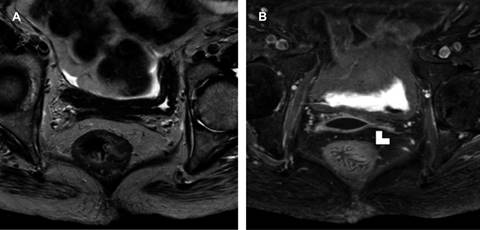

Figura 2: A) Resonancia magnética (RM) de recto en secuencia T2 en la que se observa una tumoración polipoide con aparente integridad de la muscular propia. B) RM en secuencia T1 con saturación grasa y gadolinio del mismo paciente donde se evidencia pérdida de la interfaz de la muscular propia (punta de flecha).